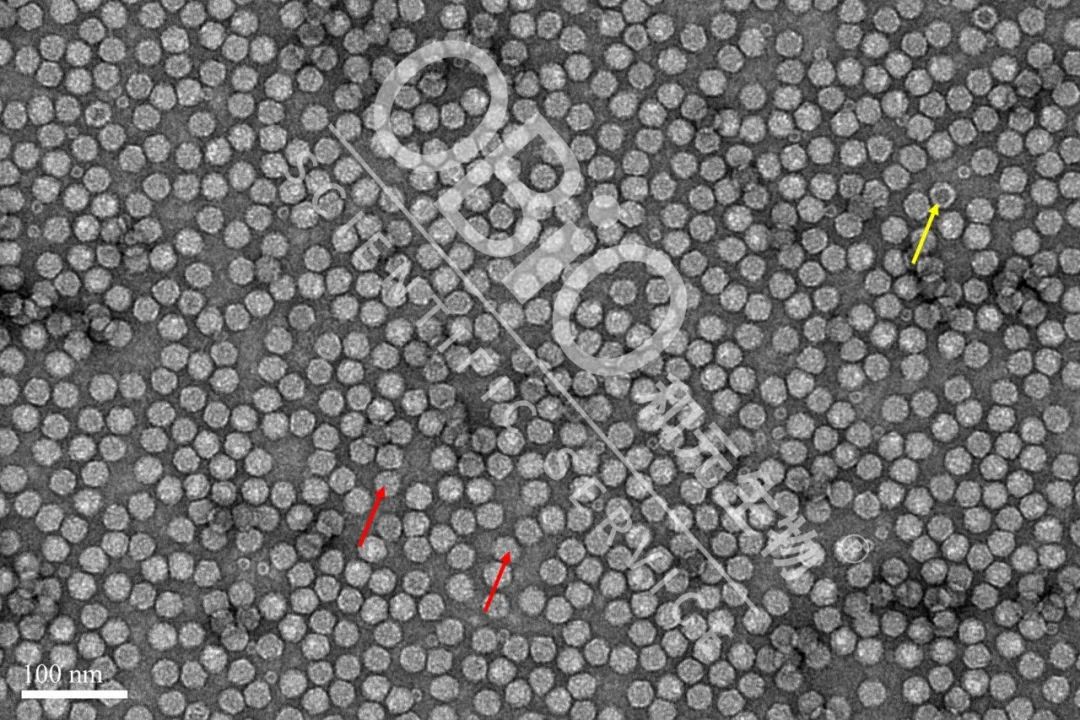

图2 银河集团官网 生物制品rAAV质粒出产空壳率

电镜后果:外包装DNADNA组的病原体颗粒肥料物状为空心颗粒肥料物状(橘红色上箭头标志);空病原体颗粒肥料物状其中有着,空洞(黄白色上箭头标志)